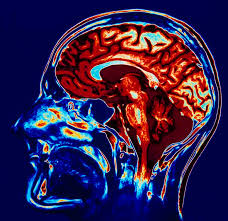

E gjithe pamja u be me e qarte kur u zbuluan kimikatet “neurotransmetuesit” ne trurin e njeriut. Truri perbehet nga biliona neuronesh ose qeliza qe duhet te komunikojne me njera tjetren.Komunikimi ndermjet neuroneve mban gjithe funksionimin e trupit, na informon ne kur nje mize na vjen ne dore ose kur ne kemi nje dhimbje. Komunikimi ndermjet neuroneve kontrollohet nga tipi dhe niveli i neurotransmetuesve. Neurotransmetuesit jane substanca kimike qe kontrollojne dhe krijojne sinjalet ne tru , brenda neuroneve edhe ndermjet tyre. Pa neurotransmetues nuk do te kishte komunikim ne tru. Zemra nuk do merrte sinjal per te rrahur dhe kembet dhe duart nuk do te dinin si te leviznin.

Duke zbuluar me shume per neurotransmetuesit ne filluam te kuptojme se kush nga transmetuesit kontrollonte disa levizje te caktuara te trupit ose kush ishte i lidhur me veshtiresi emocionale ose psikotike. Serotonina nje neurotransmetues ishte i lidhur me temperaturen e trupit dhe me onset te gjumit(Kalimi nga gjendja zgjuar ne gjendje gjumi- psh me anestezi kalon direkt ne gjendje gjumi faza para gjumit eshte ~0 s). Studimet e lidhen gjithashtu Serotoninen me depresionin dhe me vone me varietete te tjera te shendetit mendor si anoreksia dhe obsesiv-kompulsive disorder.

Studimet ne fushen e neurologjise kane gjetur mbi 50 neurotransmetues ne tru. Kerkimet thone gjithashtu qe disa nga neurotransmetuesit jane te lidhur me problemet mendore- Dopamine, Serotonin, Norepinephrine, and GABA (Gamma Aminobutyric Acid). Pak ose shume nga keta neurotransmetues dihet tashme qe prodhojne kondita psikiatrike si schicofrenia, depresioni bipolar ose obsessive-compulsive disorder dhe ADHD.

Dopamina ne zonat e mendimit ne tru mund te konsiderohet si neurotransmetuesi i fokusimit dhe thithjes se informacionit. Nivele te uleta demtojne ose dobesojne aftesine tone per tu fokusuar ne ambientin qe na rrethon domethene per tu dedikuar mnje veprimi, aktiviteti ose bisede.

Nivele te uleta dopamine e bejne fokusin dhe perqendrimin shume te veshtire dhe kjo shfaqet edhe ne semundje ADHD crregullimi me hiperaktivitet ne femijet autik. Ne anen tjeter te matjes se dopamines kur ajo fillon te rrite ne behemi shume energjik te eksituar pastaj dyshues dhe paranojik e me ne fund te hiperstimuluar nga ambienti yne.

Ne nje femije hiperaktiv(ADHD) nivelet e uleta nuk e lejojne ate te fokusohet dhe te beje ndonje gje ne ambientin qe e rrethon duke u dukur fizikisht shume aktiv dhe duke vrapuar neper dhome ose duke kaluar nga nje aktivitet ne tjetrin nga mungesa e fokusit . Kur nivelet e dopamines rriten mbi norme fokusi yne rriten ne piken qe behemi paranojik. Rritje mesatare e bejne ambientin shume stimules dhe aktivizues.